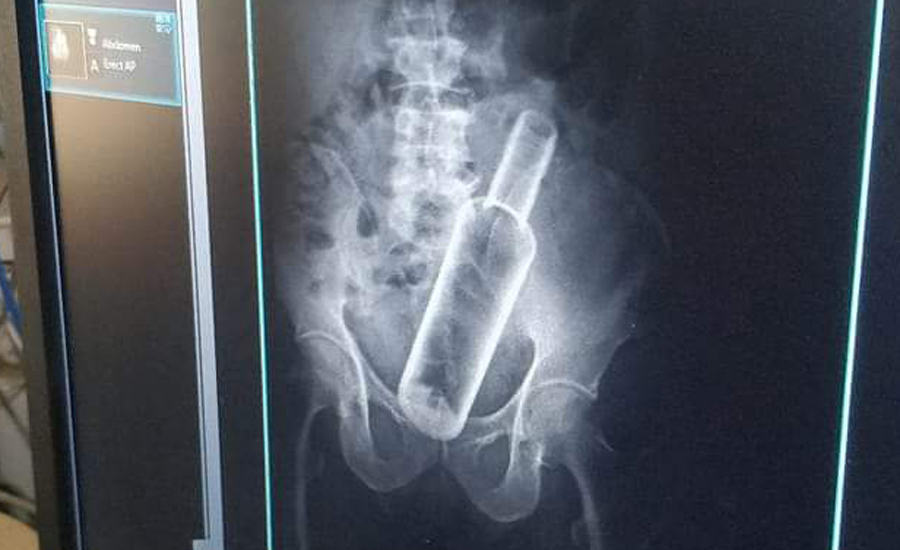

सेती प्रादेशिक अस्पतालमा उपचार गर्न गएका एक वृद्धको पेटमा बोतल भेटिएको छ ।

धनगढीको फूलबारी बस्ने ६१ वर्षीय जमनसिंह रोक्कामगरको एक्सरे गर्दा पेटमा रक्सीको बोतल देखिएको अस्पतालले जनाएको छ ।प्रादेशिक अस्पतालका सूचना अधिकारी मेखराज उपाध्यक्षले दिएको जानकारी अनुसार बिहीबार पेट दुखेपछि अस्पताल आएका रोकामगरको एक्सरे गर्ने क्रममा बोतल देखिएको हो ।

उनकाअनुसार केहि दिनअघि मदिरा सेवन गर्ने क्रममा साथीले मलद्वारबाट बोतल पेटमा घुसाइदिएको बताएका छन् । उनको प्रादेशिक अस्पतालमा उपचार भइरहेको छ ।